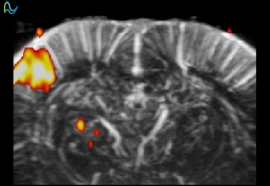

脑功能成像